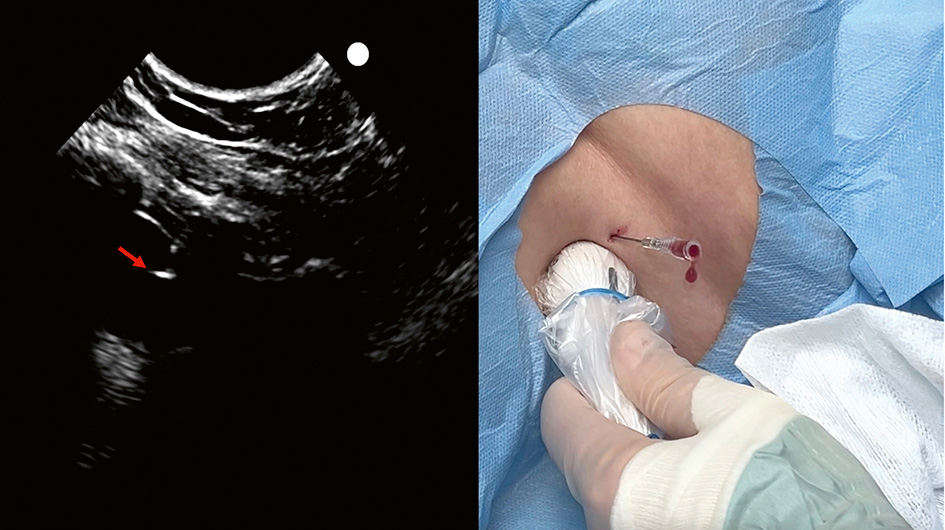

C. Under direktvisualisering (»in plane«-teknik) används först en 21G 80 mm nål för att bedöva tänkt stickkanal. I samma stickkanal införs sedan under direktvisualisering den ihåliga 18G-nålen varigenom Seldinger-ledaren matas in. I bilden ses nålspetsen (pil) som ligger i den blodiga pleuravätskan. Stickriktningen är mot diafragma, vilket är att föredra vid Seldinger-teknik eftersom dränet då oftast hamnar precis ovan diafragma. Om sticket görs från vänster i bilden förs den ihåliga ledarnålen och Seldinger-­ledaren in mot den sköra och rörliga lungan i stället för att studsa mot den mer robusta diafragmamuskulaturen.

D. Ultraljudsproben lämnas på plats till dess att Seldinger-­ledaren har införts. Då bekräftas visuellt att ledaren (pil) har hamnat i pleurarummet.